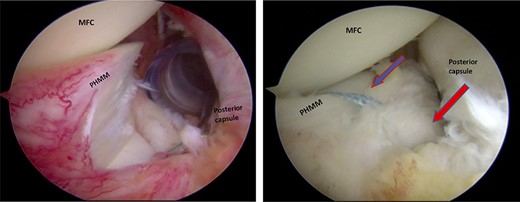

A posteromedial portal was utilized to repair both ramp tears using all-inside sutures, and curved suture hooks were inserted through the posteromedial portal. The first tear was repaired, and a non-absorbable suture was passed between the peripheral edge of the PHMM and attachment of the meniscotibial ligament (Fig. 6). The second tear was then repaired by passing the suture through the posterior capsular tissue, creating a bridge between the two tears to restore the meniscocapsular attachment (Fig. 7).

Trans-notch view of the posteromedial compartment of the left knee showing the surgical repair of the first tear. The blue arrow indicates the first lesion at the meniscosynovial junction in the red-red zone area. The red arrow shows the second tear at the meniscocapsular attachment. PHMM, posterior horn of the medial meniscus; MFC, medial femoral condyle